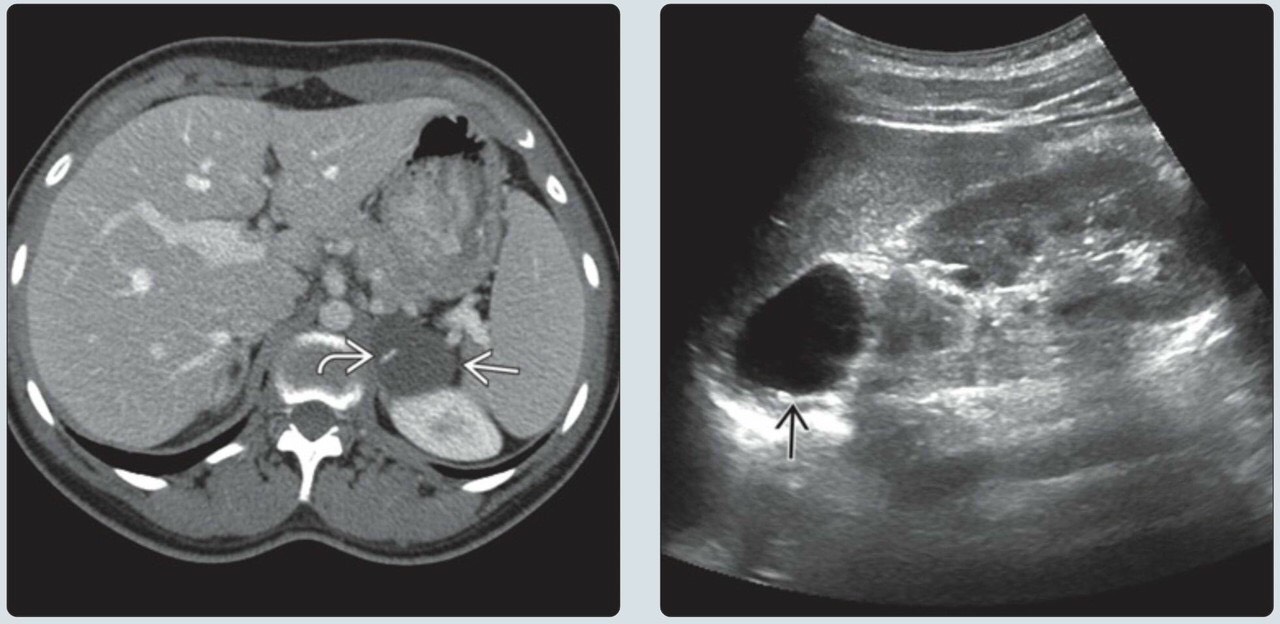

Hình ảnh nang tuyến thượng thận

Hình ảnh nang tuyến thượng thận

Hình ảnh nang tuyến thượng thận

Hình ảnh nang tuyến thượng thận